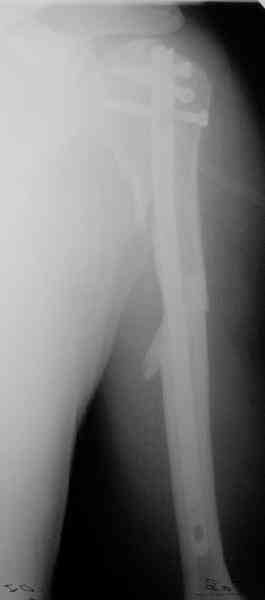

Попытка закрыто изменить положение не удалась. Передним доступом

сделали открытую репозицию, гленоид без особенностей. Временно

фиксировали спицами и остроконечным костедержателем. Фиксировали

гвоздем T2 PHN (Stryker). Для профилактики вывихов после введения

проксимальных винтов ротировали дистальный отдел кнаружи на 30

градусов как аналог остеотомии по Weber. Снимки в приложении.

Attempt of closed reduction failed. Open reduction via anterior

approach. The head was temporarily fixed by wires and sharp clamps.

Fixation by a nail - T2 PHN (Stryker). The distal fragment has been

rotated 30 degrees externally after proximal locking for dislocation

prevention as "virtual" Weber osteotomy. Images attached.